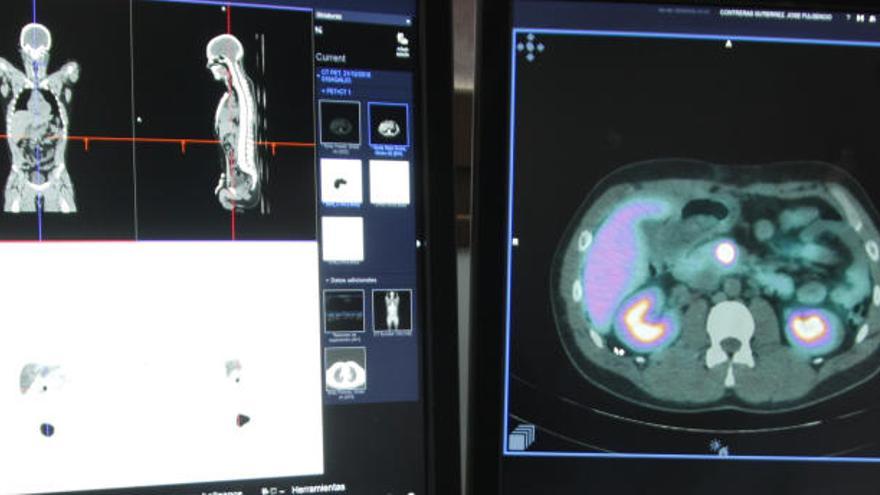

Para continuar con la investigación en una zona donde la prevalencia es menor, la Consejería de Salud hacía público ayer que la Arrixaca acaba de poner en marcha un nuevo sistema que permite mejorar el diagnóstico de cáncer neuroendocrino y evita desplazamientos a otras zonas a los enfermos.

El centro se ha convertido así en el primer hospital público del país en implantar un generador propio de germanio-galio 68, un radiofármaco de reciente aprobación para su uso en España. Porque el sistema está en otras ciudades, pero en clínicas privadas.

Desde Salud destacaban que «disponer de este fármaco va a condicionar un diagnóstico por imagen mucho más precoz y eficiente en muchos pacientes y apoyará las gestiones del Virgen de la Arrixaca para poder ser designado como Centro-Servicio-Unidad de Referencia Nacional (CESUR) en cáncer endocrino, teniendo en cuenta que este tipo de tumores son especialmente prevalentes en la Región».

En cuanto a cómo funciona, la doctora explicó que «se inyecta por vía intravenosa la dosis», tras lo cual «se espera un tiempo de reposo» tras el cual se somete al paciente a «un escáner, un barrido por todo el cuerpo», que dura de quince a veinte minutos.